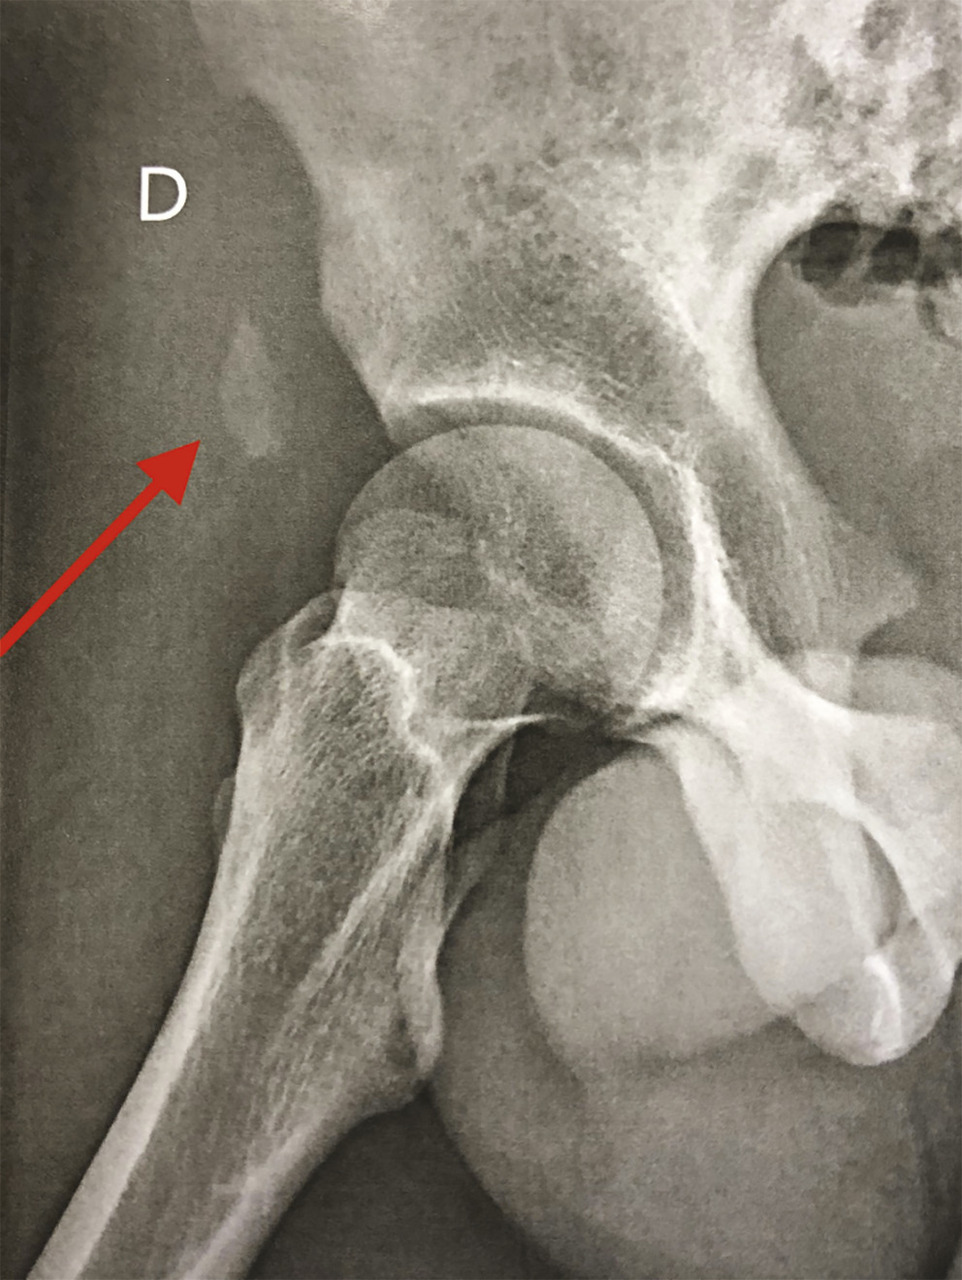

Ce jeune homme de 16 ans se présentait aux urgences pour une douleur brutale à la face antérieure de cuisse droite apparue lors d’un mouvement de tir au football. La palpation notait une voussure proximale douloureuse. La radiographie montrait une avulsion osseuse proximale de l’épine iliaque antéro-inférieure déplacée de 2,5 cm (v. figure ). Ce déplacement justifiait la réinsertion chirurgicale de cette avulsion osseuse du droit antérieur. Le patient avait totalement récupéré à 3 mois.

Le principal signe est une douleur brutale proximale de la face antérieure de la cuisse associée à un aspect de voussure pseudotumorale.1 La radiographie est souvent normale, mais si elle montre une avulsion osseuse,2 ce signe est pathognomonique. L’imagerie par résonance magnétique est l’examen de référence. Le principal facteur pronostique est le délai entre l’accident et la prise en charge.